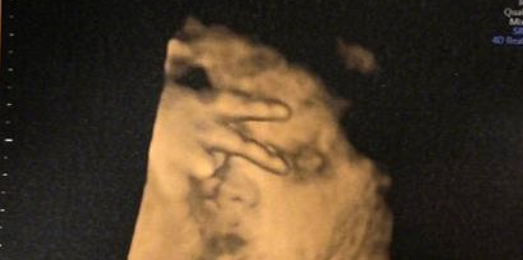

【小调皮!英国准妈妈#孕检时宝宝在肚子里比V#遮住脸[偷笑]】据外媒报道,英国的21岁准妈妈杰玛(Jemma Houston),在医院接受超声波检查,发现宝宝在脸上摆了一个“V”字手势,遮住了脸。杰玛表示,这下还得再做一次检查才能看清宝宝的脸。杰玛产检经常遇到“状况”,此前对胎儿进行性别检查时,因为宝宝的腿交叉叠在一起,所以又必须重来一次……